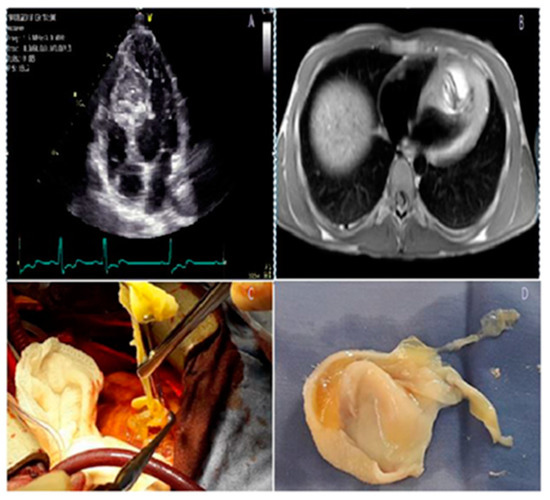

Figure 5.

A large cardiac hydatid cyst in the interventricular septum. (A) Echocardiographic frame in an apical 4-chamber view showing a large cystic mass splitting the interventricular septum (IVS). (B) Magnetic resonance image showing hydatid cyst located in the IVS. (C) Cystectomy and membrane extraction. (D) Germinative membrane. Fennira S, et al. Int. J. Infect Dis. 2019;78:31–33 [74].